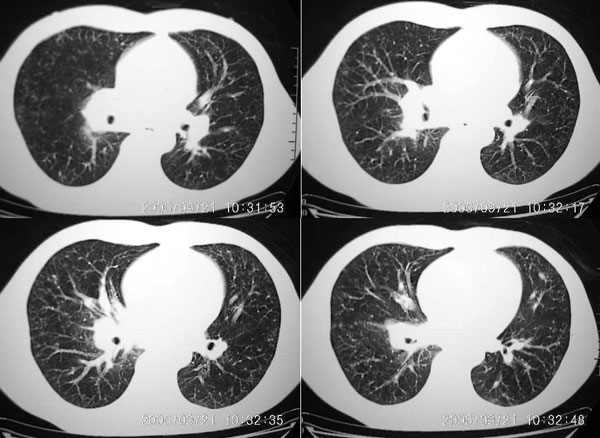

男 27岁 咳嗽一个月,治疗无效。

右肺下叶后段及右肺门附近见斑片状模糊影,密度不均,部分实变,右肺门附近见肿大淋巴结影.

两肺弥漫均匀分部粟粒壮影 右肺基底段不规则软组织密度影其内密度不均 纵隔内淋巴结钟大 请进一步右肺病灶薄层检查及补充病史后再会诊

男 27岁 咳嗽一个月,治疗无效。考虑间质性炎变,右肺下叶后基底段实质炎性结节,伴右侧肺门淋巴结肿大,不除外职业病改变,请高手指点。

两肺弥漫均匀分部粟粒壮影 右肺基底段不规则软组织密度影其内密度不均 纵隔内淋巴结肿大,考虑间质性炎变。不除外职业病改变

右肺下叶后基底段结节样病灶,边界不规则,密度不均,右肺门团片影,肺门增大,纵隔见肿大淋巴结.结合临床首先考虑:肺结核.

图像显示:右下肺门增大,伴右下肺斑片状高密度影,密度不均;右下肺支气管管壁增厚,纵隔内淋巴结肿大。意见:支气管内膜结核、结节病。建议行纤支镜检查。

右肺下叶后基底段结节样病灶,边界不规则,密度不均,右肺门团片影,肺门增大,纵隔见肿大淋巴结.考虑纵隔及肺部淋巴瘤.建议传上纵隔片.

两肺粟栗样病灶,右肺门及纵隔淋巴结增大,考虑结节病!须进一步检查免疫系统。

右下肺脊柱旁结节样肿块,可见毛刺,右侧肺门影增大,并见气管隆突前、主动脉窗内多发结节影。

右肺门影增大,纵隔内可见多个淋巴结肿大,右肺下叶内后基底段斑片状模糊影,两肺间质性改变;考虑右肺内结核并右肺门及纵隔淋巴结结核可能性大;职业病及结节病待排;肿瘤不太支持,年龄轻,无咯血,未见明显支气管狭窄,建议穿刺活检。

右下肺后基底段病灶虽然具有周围型肺癌的一些征象,但是它太虚了,纵肺比例过小,不到50%。而且在纵隔窗也显示该病灶比较虚,“块儿”比较小,内部也不实在,有小泡。

单就此病灶来说,考虑结核更为妥当。但问题是右肺门以及纵隔多组淋巴结肿大不太好解释,再有就是双肺的粟粒病灶,如果是血播的话应该有很明显的症状、体征的,不至于象楼主这般轻描淡写。

肺部有这么多病灶,临床症状却不多,我认为首先应该考虑:细支气管肺泡癌。